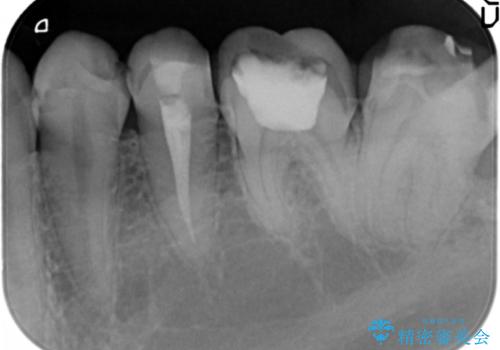

精査したところ、ほとんどの歯が保険内のレジンで充填されており、咬み合わせも悪く咬合していない歯もありました。

虫歯をしっかりと治療したのち、オールセラミッククラウンによる補綴治療を行いました。

下顎の埋伏していた親知らずも抜去しました。